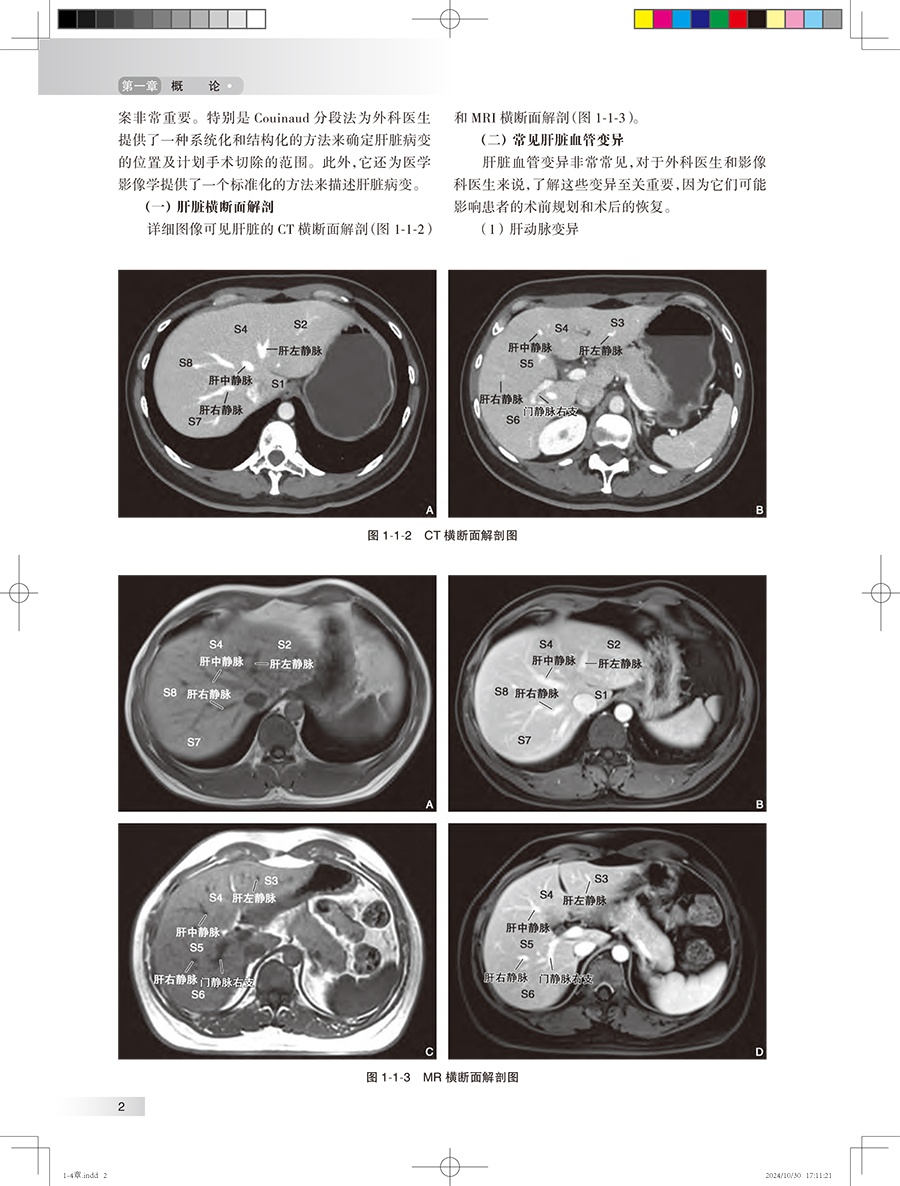

第一章 概 论/1 第一节 肝脏解剖、病理生理、疾病发病情况、影像学的价值 / 1 一、 肝脏解剖/1 二、 肝脏病理生理 / 3 三、 肝脏常见疾病的发病情况 / 3 四、 影像学的价值 / 6 第二节 胆道解剖、病理生理、疾病发病情况、影像学的价值 / 18 一、 胆道解剖/18 二、 胆道病理生理 / 20 三、 胆道系统常见疾病的发病情况/20 四、 影像学的价值 / 23 第三节 胰腺解剖、病理生理、疾病发病情况、影像学的价值 / 26 一、 胰腺解剖/26 二、 胰腺病理生理 / 27 三、 胰腺常见疾病的发病情况 / 27 四、 影像学的价值 / 29 第四节 脾脏解剖、病理生理、疾病发病情况、影像学的价值 / 35 一、 脾脏解剖/35 二、 脾脏病理生理 / 37 三、 脾脏常见疾病的发病情况 / 37 四、 影像学的价值 / 38 第五节 消化道解剖、病理生理、疾病发病情况、影像学的价值 / 42 一、 消化道解剖/42 二、 消化道病理生理 / 44 三、 消化道常见疾病的发病情况/45 四、 影像学的价值 / 46 第二章 临床症状 / 体征/54 第一节 腹痛/54 一、 腹痛的发生机制 / 54 二、 腹痛的分类及病因 / 54 三、 腹痛的临床表现 / 54 四、 腹痛的伴随症状 / 57 五、 影像学检查在腹痛诊断中的应用/57 六、 腹痛的诊断思路 / 58 第二节 腹胀/59 一、 腹胀的发生机制 / 59 二、 腹胀的分类与病因 / 59 三、 腹胀的临床表现 / 59 四、 腹胀的伴随症状 / 60 五、 腹胀的诊治思路 / 60 六、 影像学检查在腹胀诊断中的应用/61 第三节 呕吐/62 一、 定义及概述/62 二、 临床表现及诊断检查 / 63 三、 影像学在呕吐中的应用 / 63 第四节 腹泻/66 一、 定义及概述/66 二、 临床表现与诊断检查 / 66 三、 影像学在腹泻中的应用 / 67 第五节 反酸/70 一、 定义及概述/70 二、 临床表现与诊断检查 / 71 三、 影像学在反酸中的应用 / 72 第六节 嗳气/73 一、 定义及概述/73 二、 临床表现与诊断检查 / 74 三、 影像学在嗳气中的应用 / 74 第七节 吞咽困难/75 一、 定义及概述/75 二、 临床表现与诊断检查 / 76 三、 影像学在吞咽困难中的应用/77 第八节 黄疸/78 一、 定义及概述/78 二、 临床表现与诊断检查 / 78 三、 影像学在黄疸中的应用 / 79 第九节 呕血/81 一、 定义及概述/81 二、 临床表现与诊断检查 / 81 三、 影像学在呕血中的应用 / 83 第十节 便血/83 一、 定义及概述/83 二、 临床表现与诊断检查 / 84 三、 影像学在便血中的应用 / 85 第三章 肝脏影像常见征象 / 86 第一节 肝脏形态改变 / 86 一、 肝脏肿大/86 二、 肝脏缩小/91 三、 肝叶比例失调 / 94 四、 肝裂增宽/96 五、 獭尾肝/99 六、 扇贝征/101 七、 肝包膜回缩征 / 105 第二节 肝脏密度改变 / 110 一、 CT 平扫低密度 / 110 二、 CT 平扫高密度 / 115 三、 地图征/118 四、 龟背征/119 第三节 肝脏信号改变 / 120 一、 T 1WI 高信号 / 120 二、 T 1WI 低信号 / 122 三、 T 2WI 高信号 / 123 四、 T 2WI 低信号 / 125 五、 含脂病灶/127 六、 结中结/129 七、 马赛克征 / 镶嵌征 / 130 八、 门脉周围晕征 / 131 九、 簇状征/132 十、 棒棒糖征/133 十一、 靶征/135 十二、 飘带征 / 水上浮莲征 / 141 十三、 灯泡征/142 十四、 蜘蛛网征/146 十五、 轮辐征/148 十六、 繁星征/149 十七、 环礁征/151 第四节 局灶性病变强化特征 / 153 一、 速升速降/153 二、 速升缓降/156 三、 缓升缓降/160 四、 延迟强化/161 五、 环形强化/167 六、 暂时性肝脏密度 / 信号差异 / 172 七、 周边廓清征/176 八、 血管穿行征/180 九、 翻转征/184 十、 三叶草征/187 十一、 肝胆细胞期低信号 / 191 十二、 肝胆细胞期高信号 / 198 第五节 血管改变/209 一、 门静脉积气/209 二、 轨道征/211 三、 充盈缺损/212 四、 动静脉分流/214 五、 门腔静脉分流 / 217 六、 门静脉海绵样变 / 218 七、 肝静脉早显/221 八、 肝窦阻塞综合征 / 222 第四章 胆道系统影像常见征象 / 231 第一节 胆道病变/231 一、 肝内胆管扩张 / 231 二、 肝外胆管扩张 / 246 三、 肝内外胆管扩张 / 249 四、 胆管狭窄/261 五、 胆管壁增厚/268 六、 胆管肿块/275 七、 胆道积气/279 八、 剪枝征/281 九、 串珠征/282 十、 软藤征/284 十一、 杯口征/286 十二、 双管征/287 十三、 四管征/289 十四、 靶征/291 十五、 云雾征/292 十六、 中心点征/294 十七、 鸟嘴征/296 第二节 胆道病变/299 一、 胆囊肿大/299 二、 胆囊萎缩/300 三、 弥漫性胆囊壁增厚 / 302 四、 局限性胆囊壁增厚 / 305 五、 小帽征/307 六、 珍珠项链征/309 七、 瓷样胆囊/311 八、 隔膜胆囊/312 九、 双胆囊/314 十、 游离胆囊/315 十一、 高位胆囊管 / 316 十二、 低位胆囊管 / 316 十三、 胆囊窝肿块 / 319 第五章 胰腺影像常见征象 / 324 第一节 胰腺形态改变 / 324 一、 胰腺肿大/324 二、 胰腺萎缩/328 三、 胰腺局部凸起 / 332 四、 环状胰腺/336 五、 哑铃形胰腺/337 六、 分叶胰腺/338 七、 胰腺分裂/339 八、 腊肠征/340 九、 胶囊征/341 第二节 胰腺密度改变 / 343 一、 CT 平扫低密度 / 343 二、 CT 平扫高密度 / 349 三、 钙化/353 第三节 胰腺信号改变 / 359 一、 T 1WI 高信号 / 359 二、 T 1WI 低信号 / 365 三、 T 2WI 高信号 / 376 四、 T 2WI 低信号 / 386 第四节 胰管改变/398 一、 胰管扩张/398 二、 胰管狭窄/402 三、 胰管穿行 / 穿透征 / 402 四、 胰管截断征/402 五、 胰管串珠征/404 六、 胰管不相交征 / 405 第五节 肿块/406 一、 富血供肿块/406 二、 乏血供肿块/409 三、 囊性肿块/413 四、 囊实性肿块/419 五、 葡萄征/423 六、 蜂窝征/424 七、 血管穿行征/427 八、 包膜征/430 九、 浮云征/433 第六章 脾脏影像常见征象 / 437 第一节 脾脏形态改变 / 437 一、 脾肿大/437 二、 脾皮质边缘征 / 439 三、 脾楔形不强化区 / 441 第二节 脾脏信号密度特征 / 443 一、 花斑脾/443 二、 脾脏密度增加 / 444 三、 岩石脾/445 四、 脾裂隙征/447 五、 脾包膜钙化/448 六、 T 2WI 灯泡征 / 449 七、 脾气泡征(气 - 液平面) / 452 第七章 食管影像常见征象 / 456 第一节 食管管腔改变 / 456 一、 管腔狭窄/456 二、 管腔扩张/458 三、 鸟嘴征 / 萝卜根征 / 460 四、 三环征/462 五、 腔内异常/463 第二节 管壁改变/465 一、 管壁隆起/465 二、 管壁凹陷/467 三、 管壁增厚/470 四、 管壁僵硬/472 五、 充盈缺损/474 六、 龛影/476 七、 憩室/478 第三节 黏膜改变/480 一、 黏膜破坏/480 二、 黏膜平坦/481 三、 黏膜增宽和迂曲 / 483 四、 环形征/485 第四节 腔外改变/487 一、 食管压迹/487 二、 脂肪间隙异常 / 490 三、 管壁外积气/492 第八章 胃影像常见征象 / 495 第一节 胃腔改变/495 一、 胃腔扩张/495 二、 胃腔缩小/498 三、 葫芦形胃 / 哑铃形胃 / 503 四、 皮革胃/504 五、 胃扭转/506 六、 双泡征/508 第二节 胃壁改变/510 一、 胃壁隆起/510 二、 胃壁凹陷/515 三、 胃壁增厚/518 四、 胃壁僵硬/527 五、 胃壁积气/531 六、 胃壁水肿/532 七、 胃壁肿块/534 八、 龛影/536 九、 充盈缺损/539 十、 憩室/541 第三节 黏膜改变/544 一、 黏膜破坏/544 二、 黏膜平坦/546 三、 黏膜增宽和迂曲 / 547 四、 黏膜纠集/549 第四节 其他改变/550 一、 半月征/550 二、 狭颈征/552 三、 项圈征/554 四、 指压征 / 裂隙征/555 五、 环堤征/557 六、 肩胛征 / 袖口征/560 第九章 肠管影像常见征象 / 565 第一节 肠腔改变/565 一、 肠腔扩张/565 二、 动脉瘤样扩张 / 567 三、 肠腔狭窄/568 四、 肠腔高密度/571 五、 靶环征/572 六、 鹅颈征/574 七、 苹果核征/575 八、 铅管征/577 九、 咖啡豆征/578 十、 鸟嘴征/580 十一、 堆硬币征/581 十二、 哨兵袢征/584 第二节 肠壁改变/587 一、 肠壁增厚/587 二、 肠壁肿块/595 三、 肠壁气体/601 四、 分层强化(三明治征)/604 五、 肠壁憩室/606 六、 肠壁囊性 / 囊实性病变 / 608 七、 肠壁穿孔/611 八、 肠壁溃疡/614 九、 指压痕征(缺血坏死性肠炎)/616 十、 鹅卵石 / 铺路石征 / 617 第三节 肠系膜改变 / 620 一、 梳齿征/620 二、 漩涡征/623 三、 肠系膜混浊征 / 626 四、 缆绳征/629 五、 肠系膜污垢征 / 630 六、 结肠旁高密度环征(肠脂垂)/632 七、 脂肪晕征/634 八、 手风琴征/635 九、 腹茧症/638 十、 脂肪条纹征/641 十一、 脂肪环征/643 中英文名词对照索引/646 登录中华临床影像征象库步骤 / 650